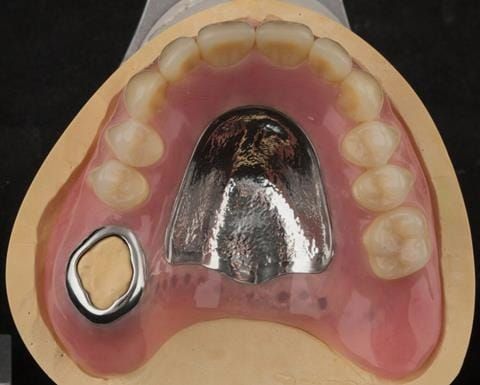

- Cobalt chromium reinforced gasket denture - using a Molloplast B "O" ring to retain and stabilise the denture. This was my professional preference as this was the least invasive and simplest solution to this dental problem. Should the UR7 require removal in the future - an artificial tooth could be added - resulting in a complete denture. The patient would have adapted to the denture fully by this stage and have good neuromuscular control of the prosthesis.

Following consultation and second discussion appointment the patient chose to have option 2 namely, a window denture - maxillary cobalt chromium based partial denture. The clinical situation and treatment process is shown in detail below with photographs. The patient was successfully rehabilitated with this and her quality of life considerably improved. The clinical work was provided by Finlay and the technical work by Rowan.